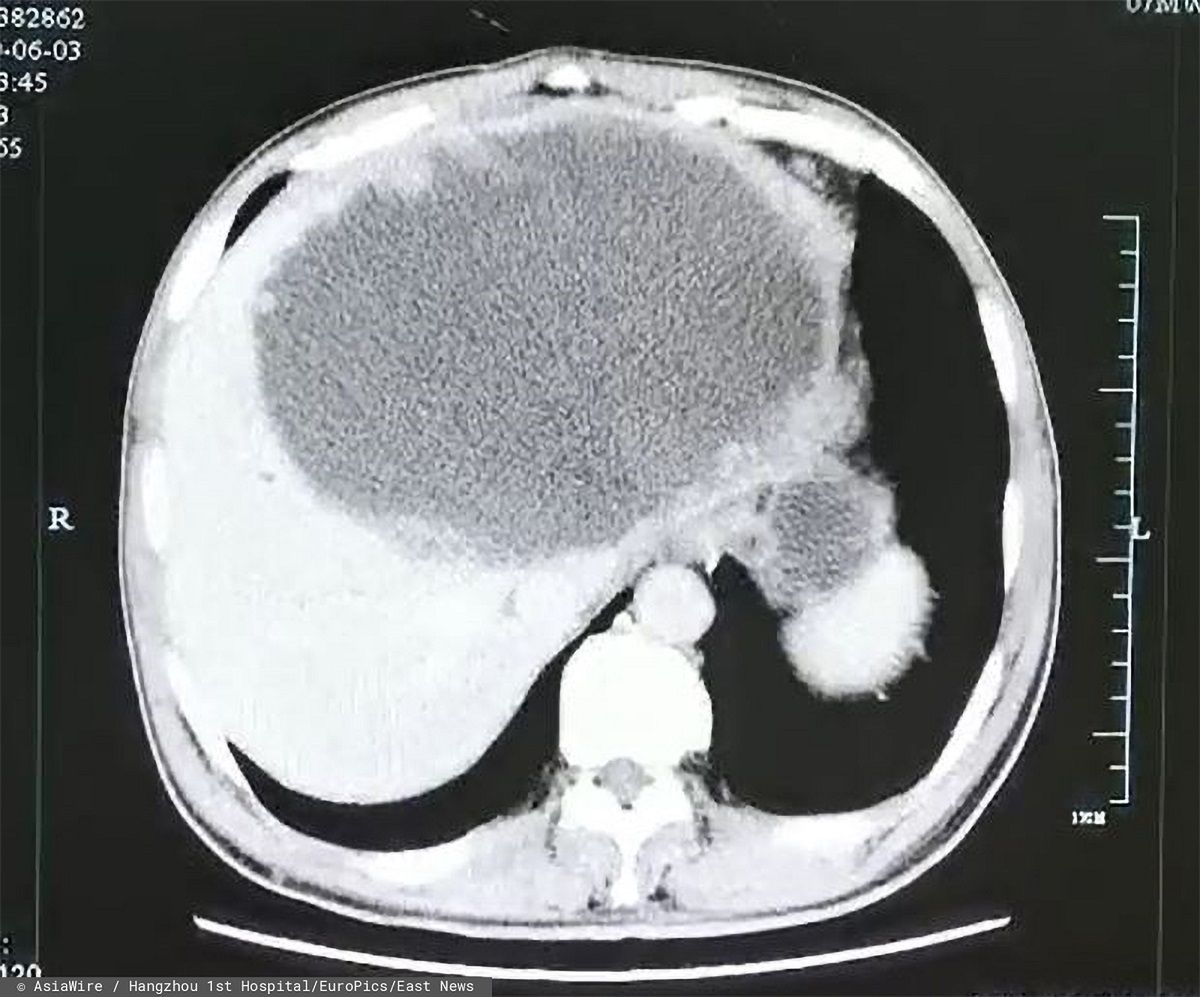

Kiedy lekarze z First People's Hospital w Hangzhou w Chinach w końcu wykonali mężczyźnie tomografię komputerową, byli mocno zdziwieni. Wykazała ona ropień o długości 19 cm oraz szerokości 18 cm w lewym płacie wątroby pacjenta. Poza tym na ścianach ropnia zaczęły rosnąć guzy.

Początkowo lekarze usunęli mężczyźnie ropień. Jednak trzy tygodnie po operacji na wątrobie wciąż były widoczne zmiany.

Ropień na wątrobie

Ropień na wątrobie © East News